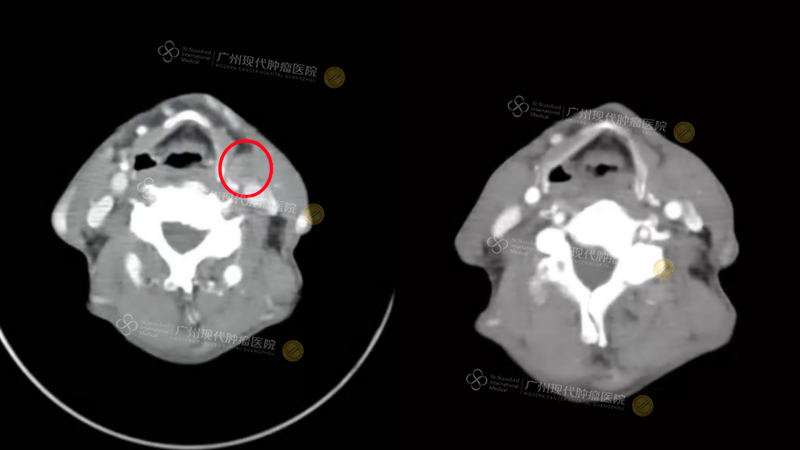

(Neck lymph node before and after treatment)

( Metastatic neck lymph node — Admission scan on April 29 vs. Follow-up CT on August 1)

Admitted in late April 2025 and successfully discharged on August 28 after undergoing six interventional therapy sessions and radioactive seed implantation at the tongue tip, Wu Wen Bor has now seen the cancer cells in both the tongue tip and neck lesions completely deactivated.“In just four months, my cancer was cured. I never expected it to be so fast—I thought it would take at least one or two years to return to a normal life.” Faced with such remarkable results, he was deeply moved and repeatedly expressed his amazement at the power of minimally invasive technology.